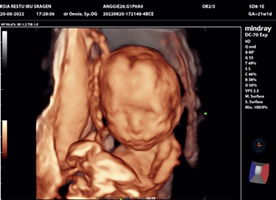

Hpht 3 April Hpl 8 Januari tpi pas d USG Hpl tgl 9 Pebruari itu yg bener yg mana ya bun?

sma bund aq jg hpht 3 April... hpl 8jan.... klo USG biasanya dilihat dri bsarnya kpla janin bund.. tp biasanya lbh akurat USG.. Krn ankq yg ke 2 jg beda 2hri dri hpl USG...

kalo menurut HPHT si iya bun 8 Januari. karna kalo USG kan di lihat dari ukuran janin nya .

Sy juga selisih 1 bulan bun Karena haid kadang gak teratur sebelumnya

Hpht 26 februari kalo USG jadi hpht 26 maret Skarang 14 week 2 day